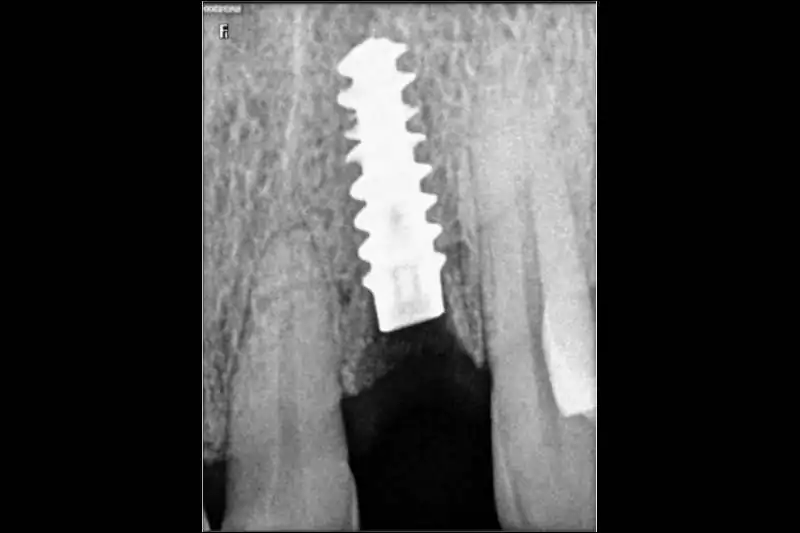

Smilex Advanced Dental Care proudly offers world-class Same Day Dental Implants Treatment in India, enabling you to regain full dental function in just one visit. Whether you've lost a single tooth or multiple, our expert implantologists use advanced digital scans, CBCT imaging, and CAD/CAM-supported restorations to provide precise, long-lasting results.

Same Day Implantology is an advanced dental procedure that allows for the replacement of missing teeth with dental implants in just a single appointment. Unlike traditional methods that involve multiple visits and a lengthy healing period, Same Day Dental Implants In India offer a more efficient and convenient solution, providing immediate results. This process involves precise digital planning to ensure the correct placement of implants, improving both the speed and success rate of the procedure. Additionally, if you’re considering a complete smile transformation, understanding the Full Mouth Dental Implant Cost In India will help you make an informed decision about this quick and effective treatment option. With modern technology and expert care, you can restore your smile in no time while maintaining long-term oral health.

Regular check-ups to ensure optimal healing and implant integration.Placement of permanent crowns once healing is complete.